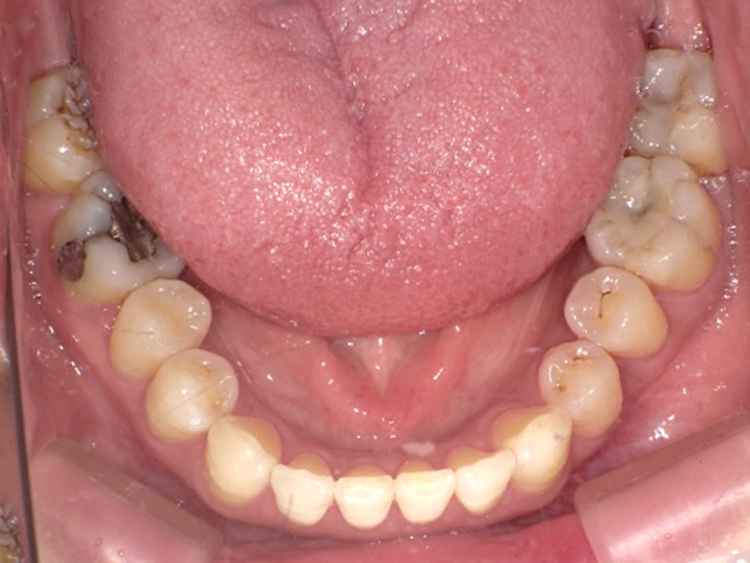

症例3

Before

After

| 主訴 | 上下の歯のガタガタを治したい |

|---|---|

| 年齢 | --- |

| 治療期間 | 約10ヶ月 |

| 治療内容 | インビザラインiGoで上下顎の治療。 狭まっていた歯並びを広げることで、 ガタガタに並んでいた歯を綺麗に並べた。 |

| 治療費 | ¥517,000(税込)+月額調整料 |

| 治療のリスク | 歯と歯の間を削ることでスペースを確保するので、 場合によっては歯が染みる症状が出ることがある。 |